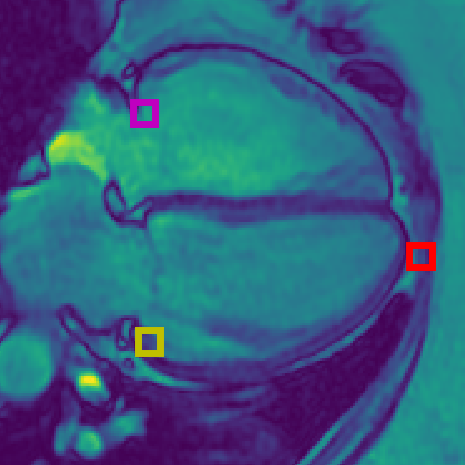

Figure 2: (a) Landmarks for Short Axis (SA) CMR: Magenta = superior right ventricle insertion point valve; Yellow = inferior right ventricle insertion point; Red = inferior lateral reflection of right ventricle free wall. (b) Landmarks for 4 chamber (4CH) CMR: Magenta = tricuspid valve; Yellow = mitral valve; Red = apex of left ventricle. (c) Subset of Landmarks included in the Cephalometric dataset [8]. Displayed landmarks are used in the aleatoric uncertainty analysis (Sec. 6.7).

We perform our experiments using three datasets. The first two datasets are from the ASPIRE Registry [33], containing Cardiac Magnetic Resonance Imaging (CMR) sequences, from a 1.5 Tesla GE HDx (GE Healthcare, Milwaukee, USA) system using an eight-channel cardiac coil. Images were acquired using a cardiac-gated multislice balanced steady-state free precession sequence (20 frames per cardiac cycle, slice thickness 10mm, 0mm inter-slice gap, field of view 480mm, acquisition matrix 256×200256200256\times 200, flip angle 60°60°60\degree, BW 125 KHz/pixel, TR/TE 3.7/1.6 ms). Each subject has a four chamber (4CH) view and/or a short axis view (SA). Each CMR sequence has a spatial resolution of 512×512512512512\times 512 pixels, where each pixel represents 0.9375mm of the organ, and the first frame was used for landmark localization in this study. There are 303 SA images, each with three annotated landmarks: the inferior right ventricle insertion point (infSA), the superior right ventricle insertion point (supSA), and the inferior lateral reflection of the right ventricle free wall (RVSA). There are 422 4CH images, each with three annotated landmarks: the apex of the left ventricle at end diastole (LVDEV Apex), the mitral valve (mitral), and tricuspid valve (tricuspid). The 4CH dataset represents a more challenging landmark localization task as the images have much higher variability than the SA dataset. The landmarks were decided and manually labelled by a radiologist, as shown in Figs. 2(a) & 2(b). For this study, we consider the SA images the EASY dataset, and the 4CH images the HARD dataset.